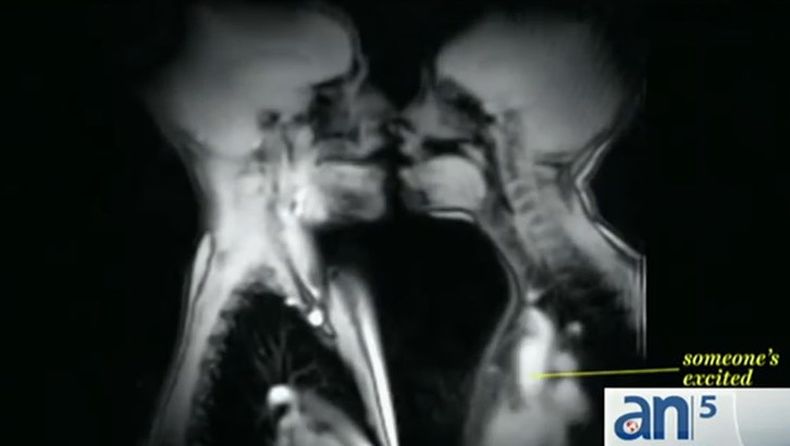

Resonancia magnética revela los misterios del sexo